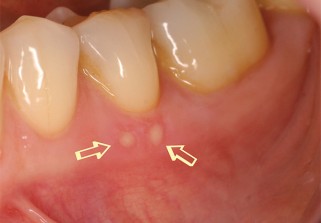

On sait tous ce que sont les aphtes, enfin on croit le savoir. Pourtant, on les confond souvent

avec d’autres lésions de la bouche ou même des infections oropharyngées… Chassons les idées reçues !

L’aphte est un trouble vasculaire. L’occlusion d’une artère nourricière et la perméabilité de ses parois induisent la nécrose d’une petite zone et une inflammation associée. Cela finit par faire un trou. C’est ça, un aphte ! Plus l’artère est importante, plus la zone nécrosée est étendue, et plus l’aphte est gros. Il existe aussi une maladie (dite de Behçet) qui se manifeste par des aphtes buccaux et génitaux. Elle atteint surtout la population du pourtour méditerranéen et du Japon.

Un aphte ne saigne jamais, puisque c’est un tissu en train de mourir. Un aphte qui saigne, c’est autre chose qu’un aphte ! De même si cela dure plus de quinze jours, ce n’est pas un aphte non plus.

5. Tout ce qui brûle dans la bouche est un aphte

FAUX

Pour beaucoup, les lésions buccales sont soit des aphtes, soit des mycoses. Or, il existe quantité de lésions qui peuvent être traumatiques, infectieuses, auto-immunes, allergiques, dues à des affections hématologiques.